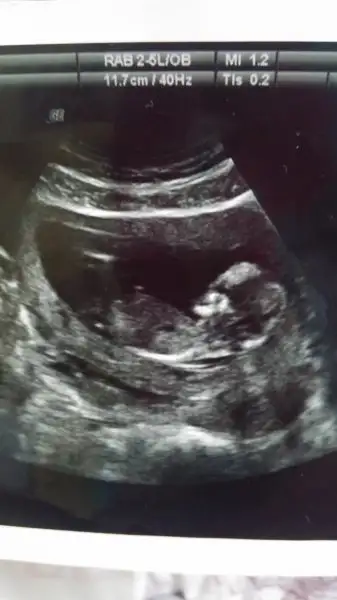

kızlar cinsiyet için bakar mısınız?